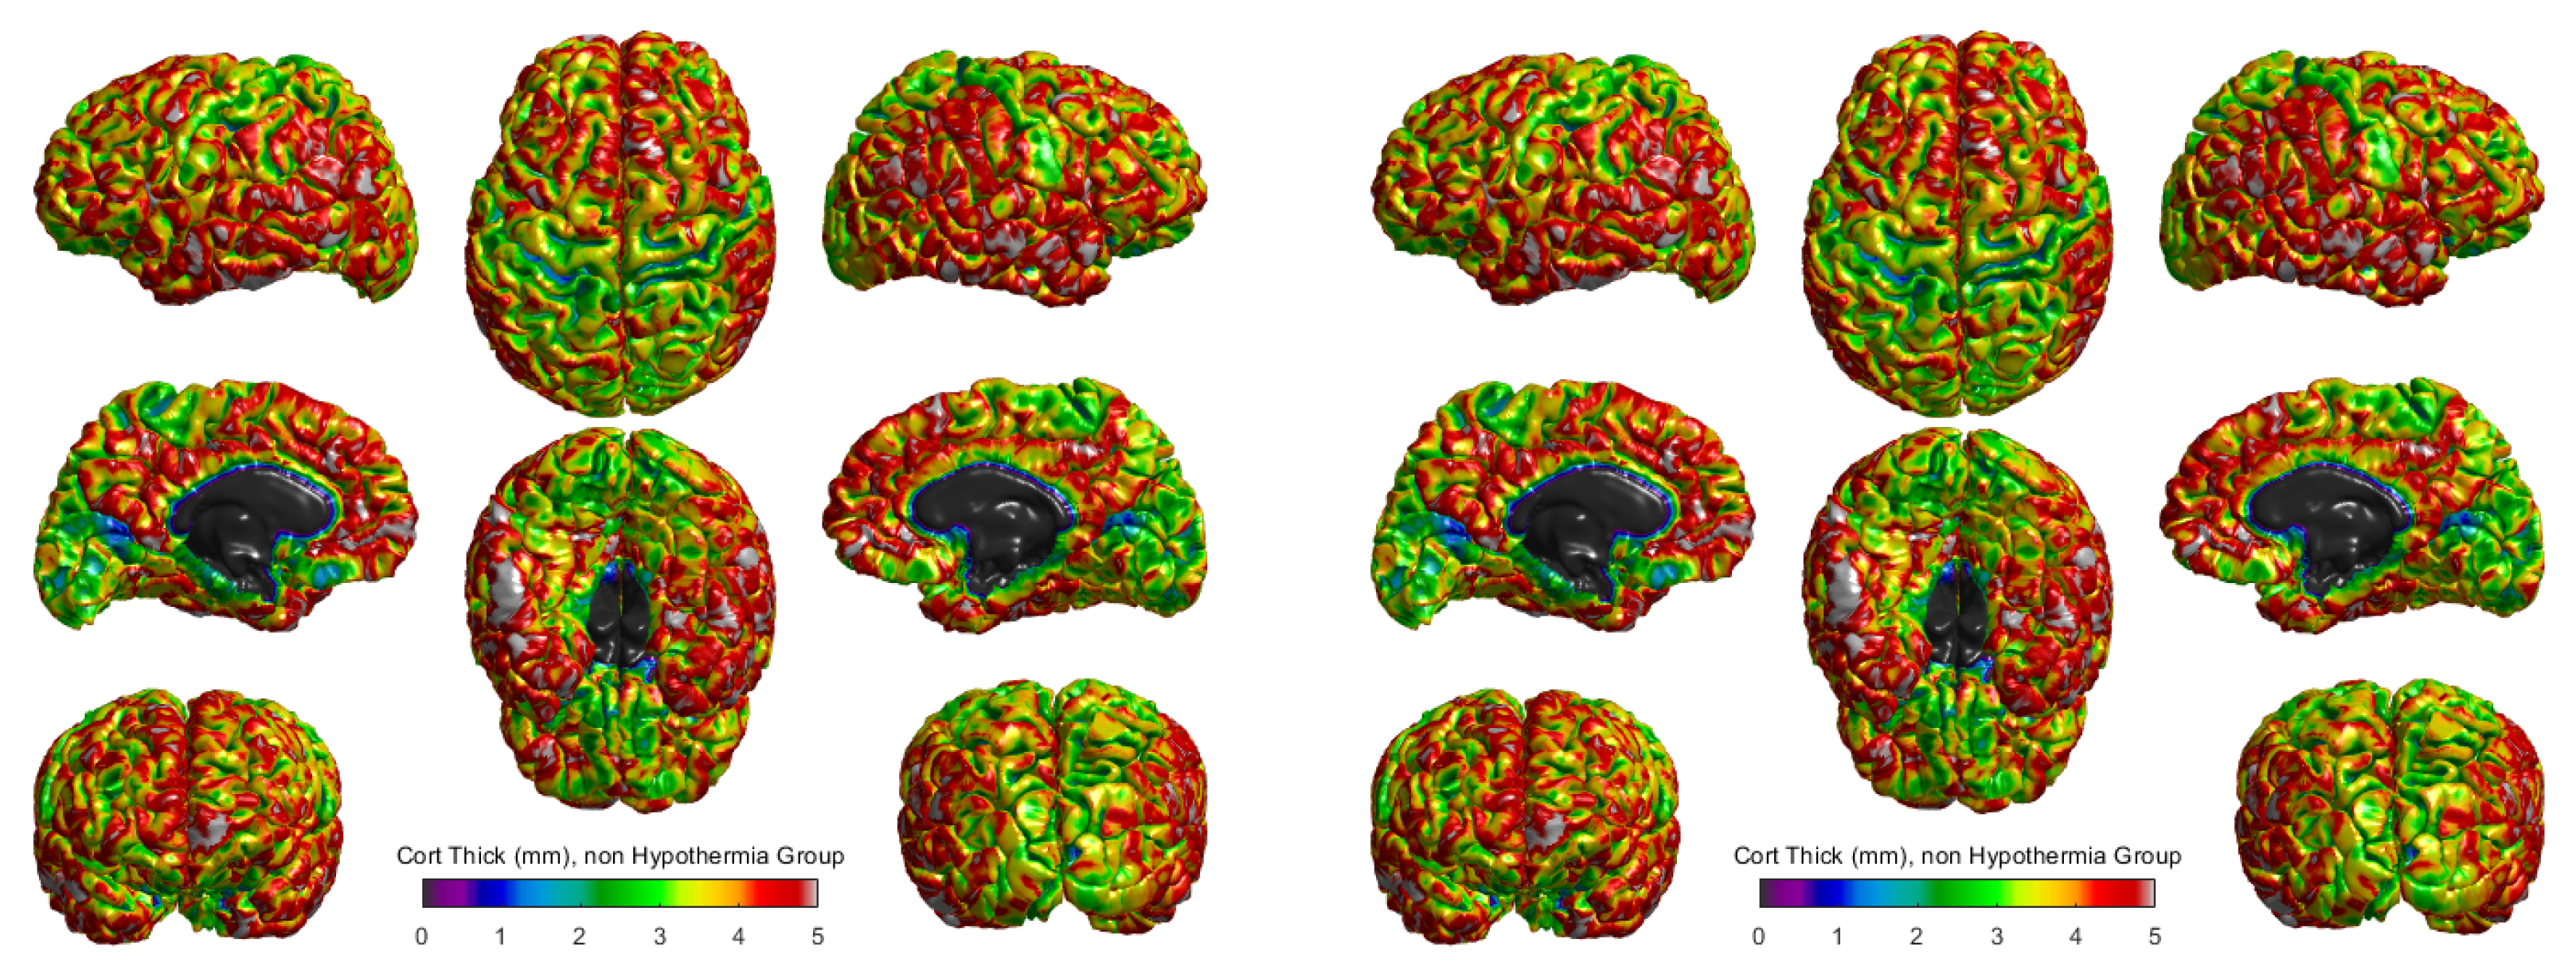

The cortical thickness for the hypothermia-treated group and the non-hypothermia group was compared using 3D surface reconstructions (Figure 3). In the hypothermia-treated group (Figure 3 right), a heatmap of cortical thickness revealed a higher degree of preservation, with thicker regions primarily located in the central sulci and occipital areas. The cortical thickness ranged from 0 mm to 5 mm, with the highest values represented in red and the lowest in blue. These results suggest that therapeutic hypothermia promotes cortical growth or maintenance in these critical areas.

Conversely, the non-hypothermia group (Figure 3, left) exhibited more widespread cortical thinning, particularly in the frontal and parietal lobes. These regions, responsible for cognitive and motor functions, showed reduced cortical thickness, indicating the potential for developmental delays or impairments in this untreated population. The comparison of these two groups highlights the differential effects of therapeutic hypothermia, suggesting a neuroprotective effect in preserving cortical structure post-injury.

The Figure 3 shows cortical thickness measurements in millimeters for two groups of term neonates: those who did not receive therapeutic hypothermia (left panel) and those who did (right panel). The scale ranges from purple (indicating thinner cortical areas) to red (indicating thicker cortical areas), with a scale of 0 to 5 mm. Visual comparison between the two groups suggests differences in the distribution and extent of cortical thickness across various brain regions. In the hypothermia-treated group, thicker regions (represented by green to red hues) appear more pronounced and widespread, particularly in motor and sensory processing areas. In contrast, the non-hypothermia group displays a greater prevalence of thinner regions (depicted in shades of blue and purple), suggesting that therapeutic hypothermia may help preserve or promote greater cortical thickness. This preservation of cortical structure might correlate with improved neurodevelopmental outcomes, as larger cortical thickness has been associated with better cognitive and motor functions in previous studies. However, further quantitative analysis would be required to confirm these observations and assess their statistical significance. Additionally, these visual insights highlight the importance of therapeutic interventions in mitigating the effects of hypoxic-ischemic encephalopathy (HIE) on brain development.